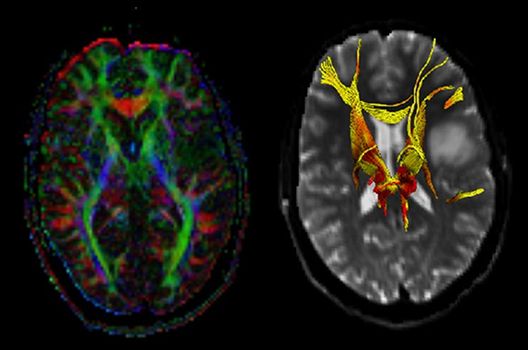

- MR-Diffusionstensorbildgebung (Faserbahndarstellung/fiber tracking)

Die Schwerpunkte in der MR-Forschung liegen in der multiparametrischen und funktionellen Bildgebung bei onkologischen und anderen, neuroradiologischen Fragestellungen und umfassen die Anwendung modernster MR-Verfahren sowie die Untersuchung an Hochfeld-Geräten.

Die Magnetresonanztomographie (MRT) ist ein Verfahren, bei dem durch magnetische Kräfte Bilder des Körperinneren angefertigt werden. In der Neuroradiologie können manchmal kleinste Veränderungen schwere Folgen haben; daher forschen wir an der Entwicklung hochauflösender MRT-Sequenzen, mit denen diese Prozesse und auch einzelne Nervenfaserbahnen sichtbar gemacht werden können. Darüber hinaus sind bei vielen Erkrankungen des Gehirns die Blutgefäße betroffen. Daher arbeiten wir an der Neu- und Weiterentwicklung von MRT-Sequenzen zur Darstellung der Blutgefäße und zur Blutflussanalyse (sog. „Angio-MRT“). Einen besonderen Forschungsschwerpunkt unserer Klinik stellen die MR-Protonenspektroskopie und die funktionelle MRT dar, mit denen die Analyse einzelner chemischer Substanzen im Hirngewebe oder die Darstellung ausgewählter Hirnfunktionen möglich ist.